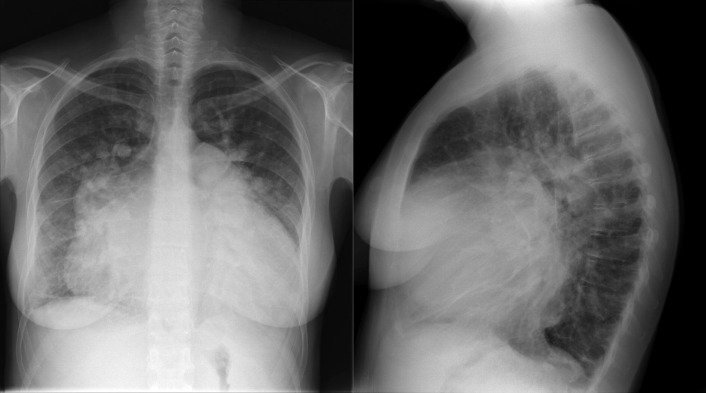

A patent foramen ovale is present in 25% to 30% of the adult population ( Figs. 18-1 to 18-4 ). Any magnitude of shunting across it in normal circumstances is undetectable radiographically. Percutaneous patent foramen ovale closure devices are fairly commonly inserted and are radiographically evident.

See Figures 18-5 to 18-31 . Possible findings are discussed in the following sections.